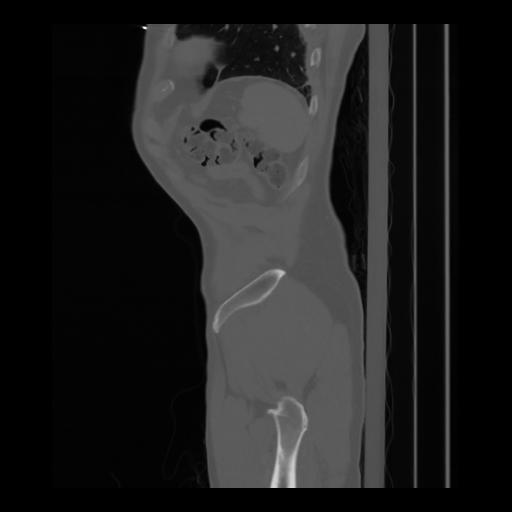

36 CUERPO,CE,Sagittal,3.000,CUERPO,Sagittal,